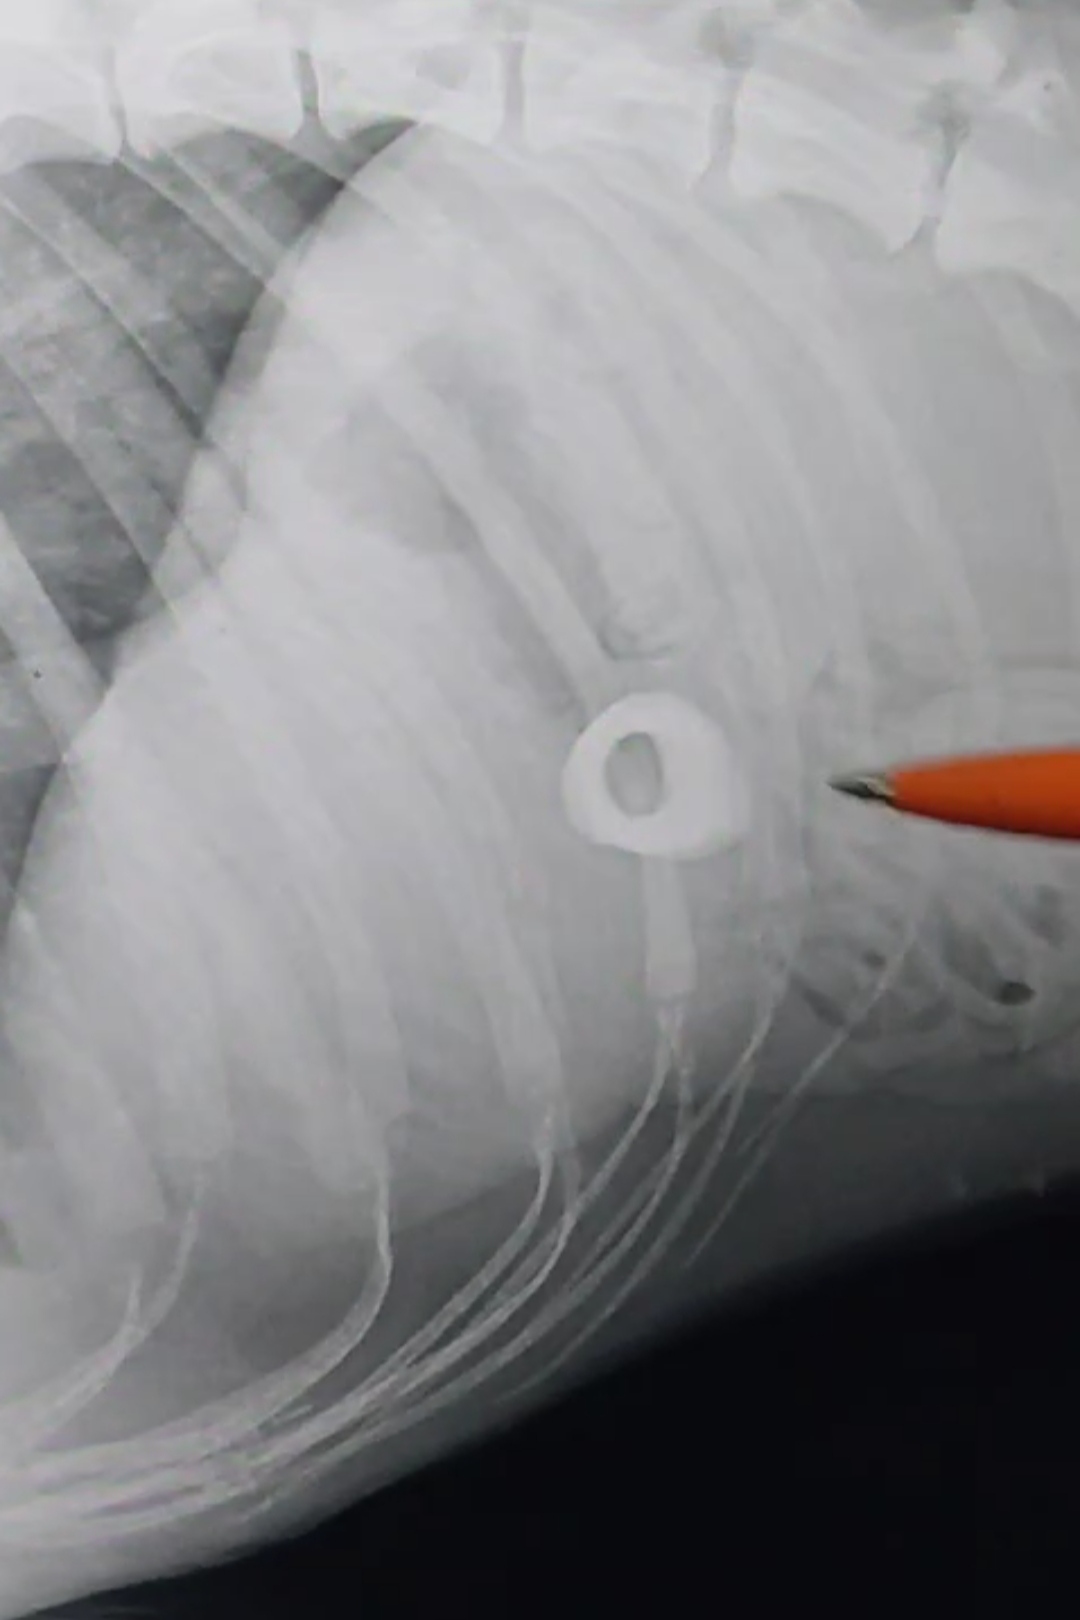

Когда хозяйка Татьяна Ямова отвезла Догора из Бердигестяха Горного улуса в Якутск, пес уже находится в тяжелом состоянии. В «Поливете» начали диагностику и лечение острой почечной недостаточности. Рентген собаке сделали 19 марта, где выявили, что Догор проглотил крупную кость. Был поставлен диагноз: перфорация желудочно-кишечного тракта, то есть образование отверстия в стенках ЖКТ.